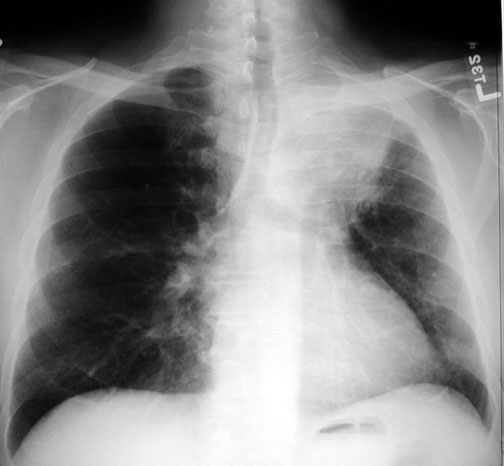

Case 1 Labeled Image What are the conditions where you get thin walled cavities?